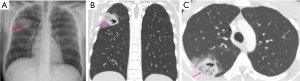

Mycobacterium TB infection

Cavitation is a hallmark of post-primary TB, occurring in approximately 50% of patients (7). The likelihood of cavitation correlates with higher sputum mycobacterial loads (8). Moreover, cavitation is an uncommon feature of primary TB, which is characterized by inflammation and granuloma formation that does not usually lead to the tissue destruction that causes cavitation (8,17). Cavitation primarily occurs in post-primary TB, when the bacteria reactivate from dormant state and the immune system’s response leads to more extensive tissue damage and cavitation (8,17). Hence, radiologically, primary TB is more likely to show intra-thoracic lymph node enlargement, pleural effusion and lower lobe lung lesions. Cavitation is less characteristic of these initial presentations, seen only in 10–30% of cases (17). Typical imaging findings of post-primary TB include a predilection for the upper lobes, particularly the apical and posterior segments (7). Patchy and poorly defined consolidations are often the earliest findings (7,8). Cavities often form within areas of consolidation, exhibiting variable wall thickness, ranging from thin and smooth to thick and nodular walls (Figures 7-9) (8). Air-fluid levels are seen in 10–20% of tuberculous cavities (18). Endobronchial dissemination can lead to tree-in-bud opacities, and pleural effusion is common (8).